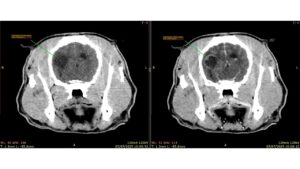

Convulsão em cães e gatos: é idiopática ou não? Como a tomografia de crânio pode